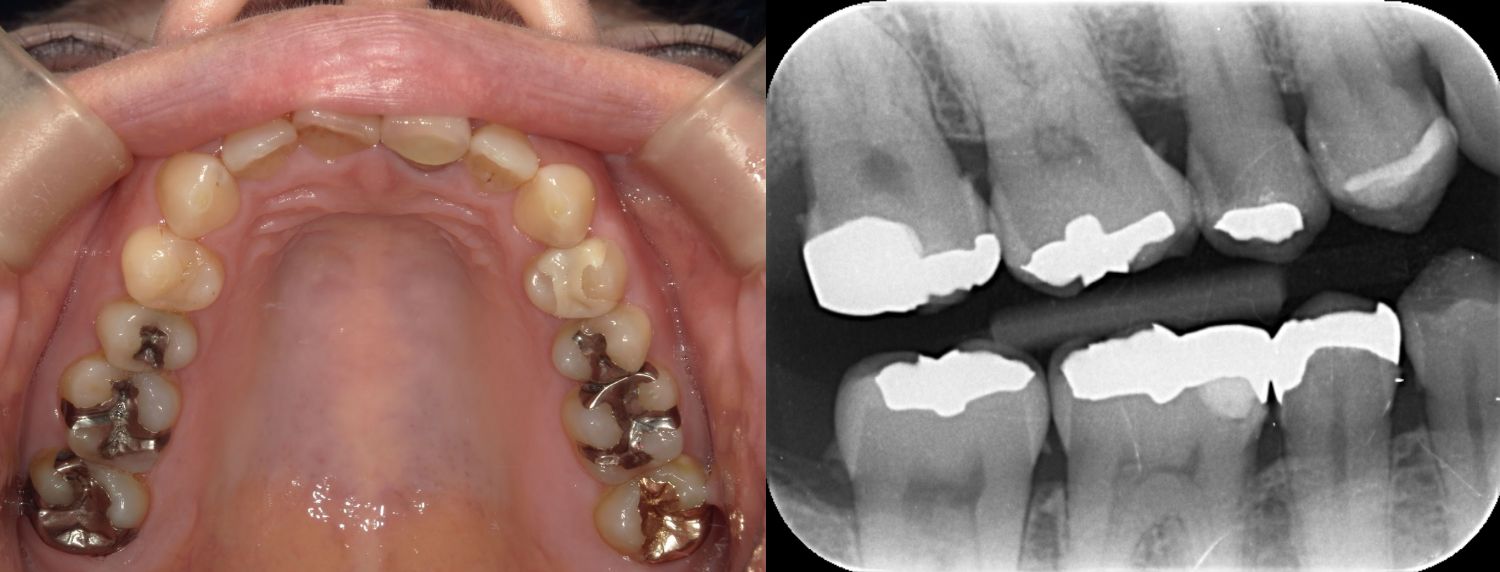

2025/04/22 セレック

MY2619様

通院時年齢 53歳

性別 女性

通院目的 虫歯なのか、たまに痛むが歯科恐怖症で怖い

診断 ①重度歯周炎

②う根面からの歯髄近接う蝕

処置内容 (または主訴) ①歯周治療(SRPまで)

②MTAセメントを用いた歯髄温存慮方法からセレックにて修復

通院期間 ①1年(歯周病治療)

②セレック1日

費用

①重度歯周炎 保険請求の範囲内

②う根面からの歯髄近接う蝕 MTAおよび一次的神経保護44,000円

セレック77,000円

リスク・副作用

①歯周病は定期的なメンテナンスが必要で歯ブラシを怠ると根面う蝕や歯周病の再発があります。

②神経を温存しておりますが、神経症状が生じた場合には抜髄と言って神経を除かなくてはならないことがあります。

処置後知覚過敏が生じることがあります。